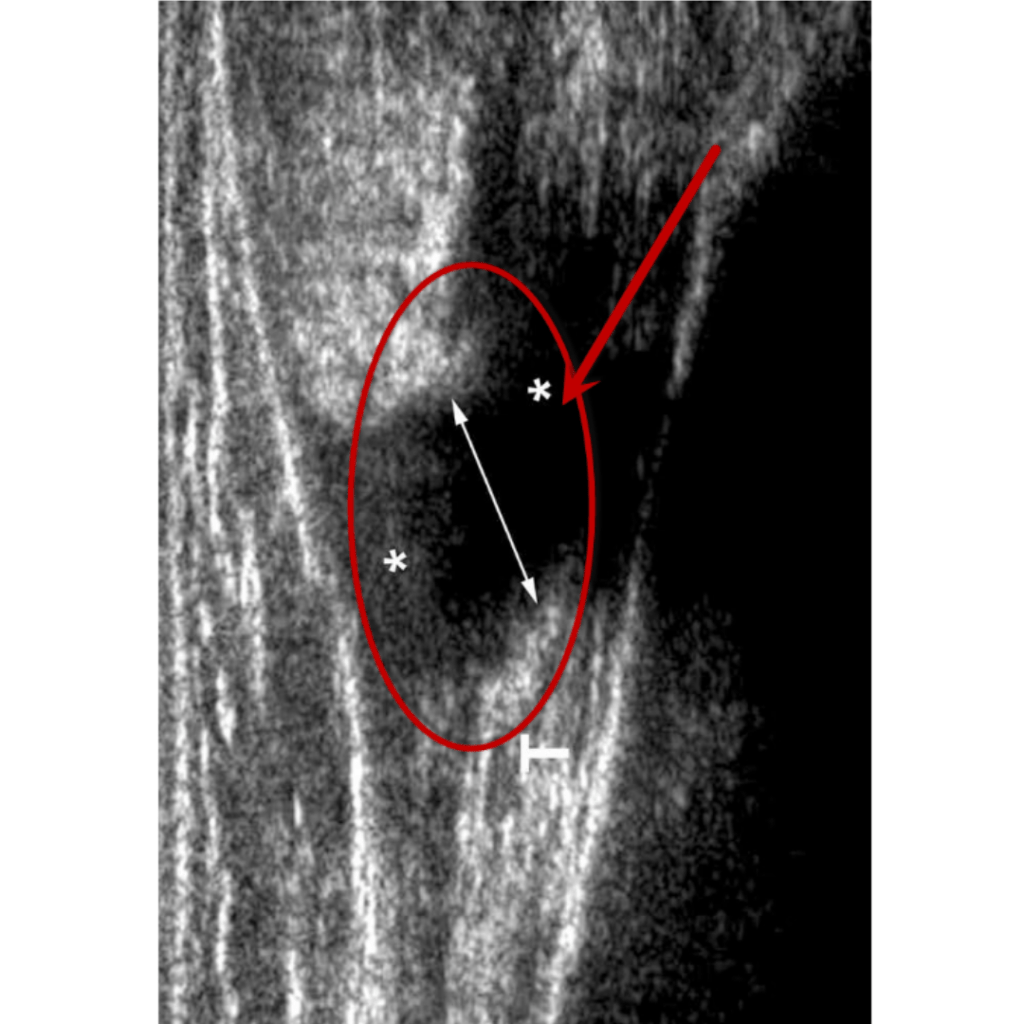

Ultrasonido

Ruptura total Grado III